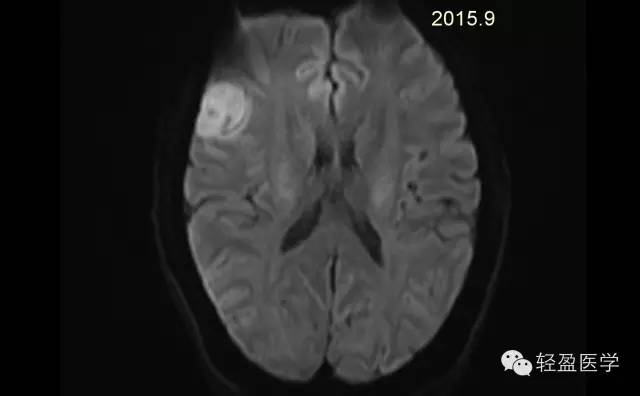

【病例】颅内肿瘤,脑内?脑外?

病理为:小细胞恶性肿瘤,考虑为(外周)原始神经外胚层肿瘤,(复发)。以下是病例结果及分析。